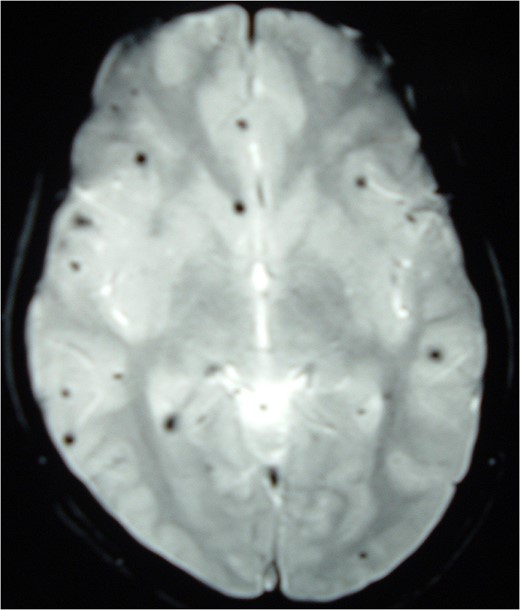

MRI Brain (GRE T2WI) showing multiple hypointense lesions diagnosed as cerebral cavernomas.

Intramedullary spinal cavernomas may be associated with multiple concurrent occult cerebral cavernomas as seen in our case. This makes MRI of the complete neuraxis a crucial next step [1, 4, 5]. Familial CM syndrome should be suspected for any case with multiple cerebral cavernomas [4]. MRI remains the gold standard for diagnosing both cerebral and intramedullary cavernomas. They appear as mixed signal intensity lesions in on T1 and T2-weighted images surrounded by a low-signal intensity zone (due to hemosiderin deposits) best seen on T2-weighted images [4, 5, 8].